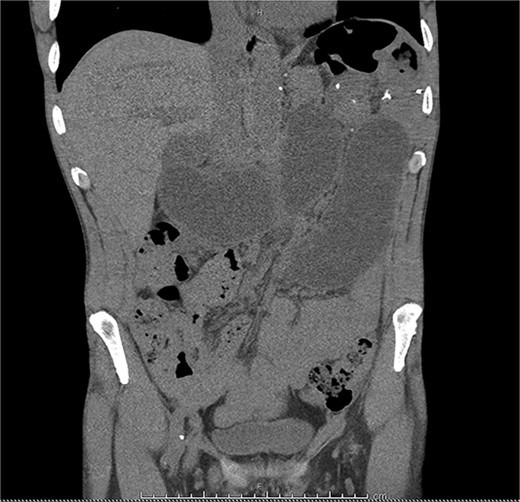

Mr R was a 55-year-old male who presented to a local hospital with abdominal pain 10 years after radical total gastrectomy for adenocarcinoma with Roux-en-Y reconstruction. Computed tomography (CT) showed a small bowel internal hernia (IH) with evidence suggestive of bowel ischemia (Fig. 1). A small bowel IH is a rare but dreaded complication following Roux-en-Y in which a segment of small bowel protrudes through a defect in the peritoneum or mesentery (Fig. 2). IH is thought to occur in ˂5% of cases, though prompt diagnosis and surgery of IH are essential as delayed treatment may lead to bowel strangulation and perforation.

A CT scan of the patient’s abdomen demonstrating obstruction suggestive of internal hernia.